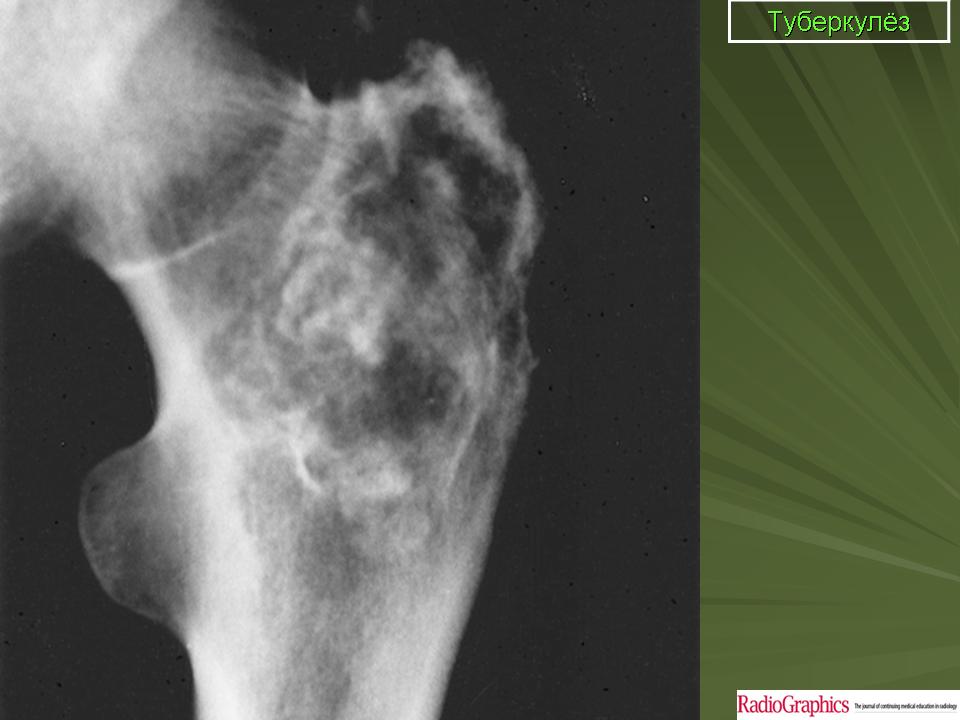

Медицинские аспекты заболеваний: рентгенологическая картина туберкулеза костей

Раздел: Снимки-откровения